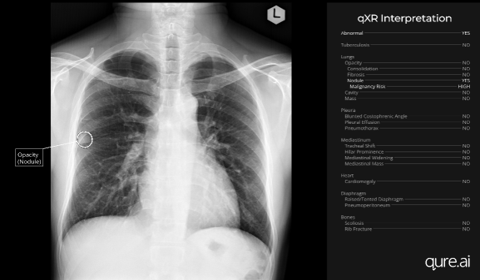

The case series, "Chest X-Ray Analysis with Artificial Intelligence Software Aids in the Early Diagnosis of Lung Cancer," conducted at Hacettepe University in Ankara, Turkey, used data from the CREATE study — a coordinated, five-country research initiative. The three highlighted cases showed how AI-flagged suspicious nodules in patients with no prior suspicion of lung cancer. They had entered the chest X-ray imaging pathway via the emergency room with fever; as a routine radiology CXR prior to treatment for ulcerative colitis; and CXR as part of a routine smoking cessation program. The AI-powered finding enabled timely referral for CT imaging confirmation and biopsy, confirming early-stage lung cancer in all cases. Each patient underwent curative surgical intervention with favourable outcomes.

- Expanding the diagnostic funnel — AI-driven detection on non-screening X-rays identifies patients who would otherwise fall outside current screening criteria such as age or smoking history.